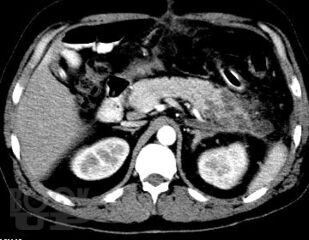

Острый панкреатит. Современные принципы диагностики и лечения

Учебно-методическое пособие посвящено актуальным проблемам этиологии, патогенеза, диагностики, современным методам консервативного и оперативного лечения острого панкреатита Представлены новые классификации, схемы консервативного лечения, современные виды оперативного лечения. Иллюстрировано рисунками, таблицами, имеются тестовые задания и задачи. Пособие предназначено для ординаторов и слушателей дополнительного профессионального образования, обучающихся по специальности 31.08.67 Хирургия.